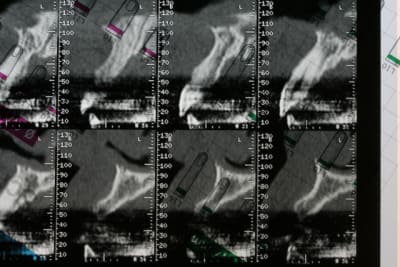

bon, première salve...

photos du scanner...et avec la planche radio pour bien estimer le volume disponible

d'entrée de jeu, on peut se dire que çà va être plus coton pour la 22 que pour la 12 car on à moins d'épaisseur et la corticale est plus dense...